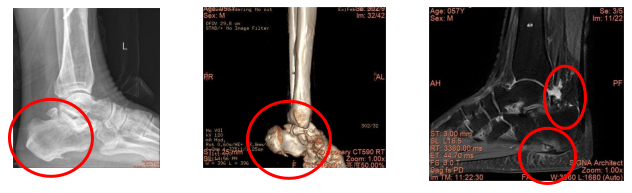

57歲的陳先生因左踝關(guān)節(jié)后側(cè)疼痛半年,且疼痛程度逐漸加重,現(xiàn)影響行走,就診于我院手足外科。經(jīng)檢查,陳先生有左踝關(guān)節(jié)撞擊綜合征、左距后三角骨、左跖筋膜炎、左跟骨骨刺、左距骨軟骨損傷等多種病癥。

術(shù)前檢查發(fā)現(xiàn)后踝三角骨撞擊,跖筋膜炎